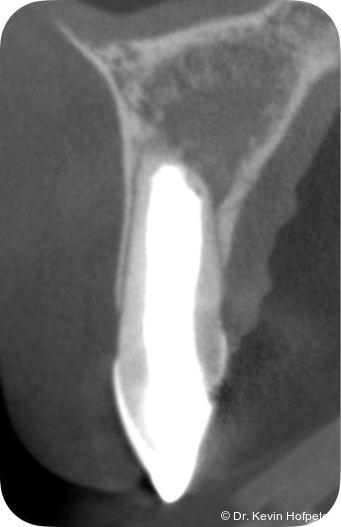

Zwei Monate später konnte die definitive Obturation erfolgen. Da der Kanal nun trocken war, konnte die Dentinbrücke im apikalen Bereich unter Sicht entfernt werden (Abb. 3). Das Mineral Trioxid Aggregat (MTA, Medcem) wurde frisch mit steriler Kochsalzlösung angemischt und mithilfe einer MTA-Gun (MAP-System, Produits Dentaires) sowie individuell angepassten Guttaperchastiften in den gekrümmten Kanalabschnitt eingebracht. Die größte technische Herausforderung bestand im Einbringen eines dichten apikalen MTA-Verschlusses hinter der Kurvatur (Abb. 4). Nachdem dieser Verschluss gesetzt war, wurde der restliche Kanal mit einem Epoxidharz-Sealer (AH Plus, Dentsply Sirona) und erwärmter Guttapercha mittels warm-vertikaler Kompaktion gefüllt und der Zugang adhäsiv verschlossen (Abb. 5).